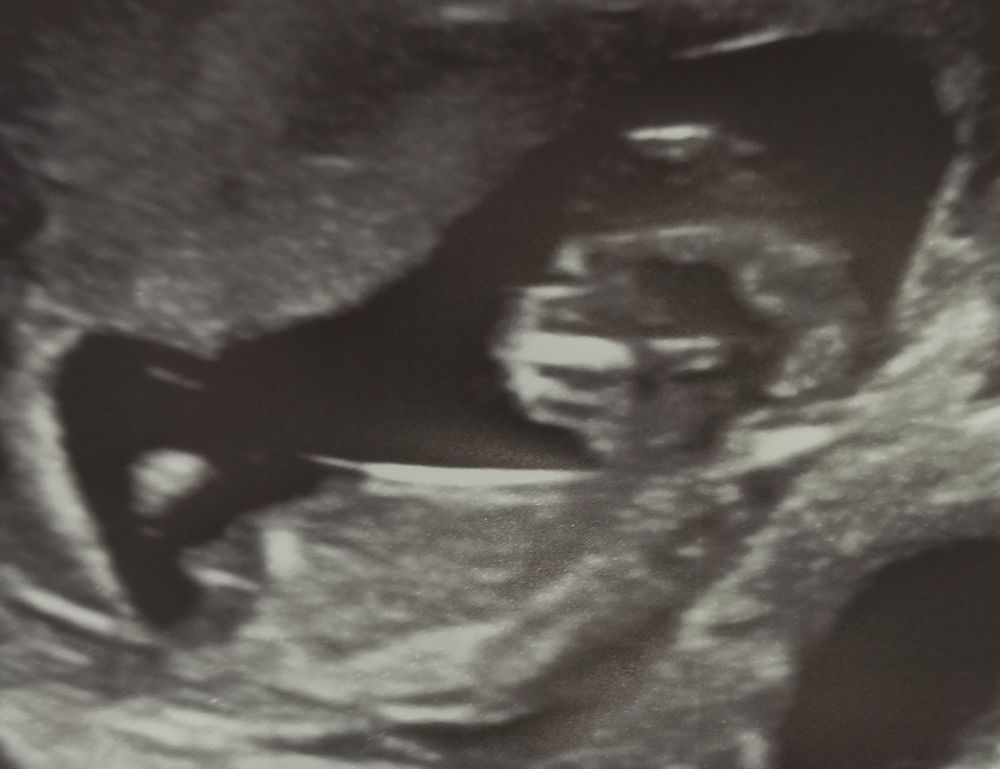

УЗИ 72 дпо (12+1) ❤🤞🤞🤞

По М 12+1 и ПДР на 8 ноября, по УЗИ опережаем на 5 дней - 12+6 и ПДР 3 ноября. Врач так и пишет в заключении УЗИ тахикардию плода, но уже до 175 уд/мин в этот раз, неделю назад было до 180 уд/мин. Домашним допплером утром пишет от 158 до 170 уд/мин. Надеюсь, что с каждой неделей, постепенно, будет замедляться ЧСС. На платное УЗИ теперь планирую сходить в 16 недель.

По фото с УЗИ не видно половых бугорков, но я и не настаивала их высматривать, зачем, ведь всё равно уже известно по анализу крови.